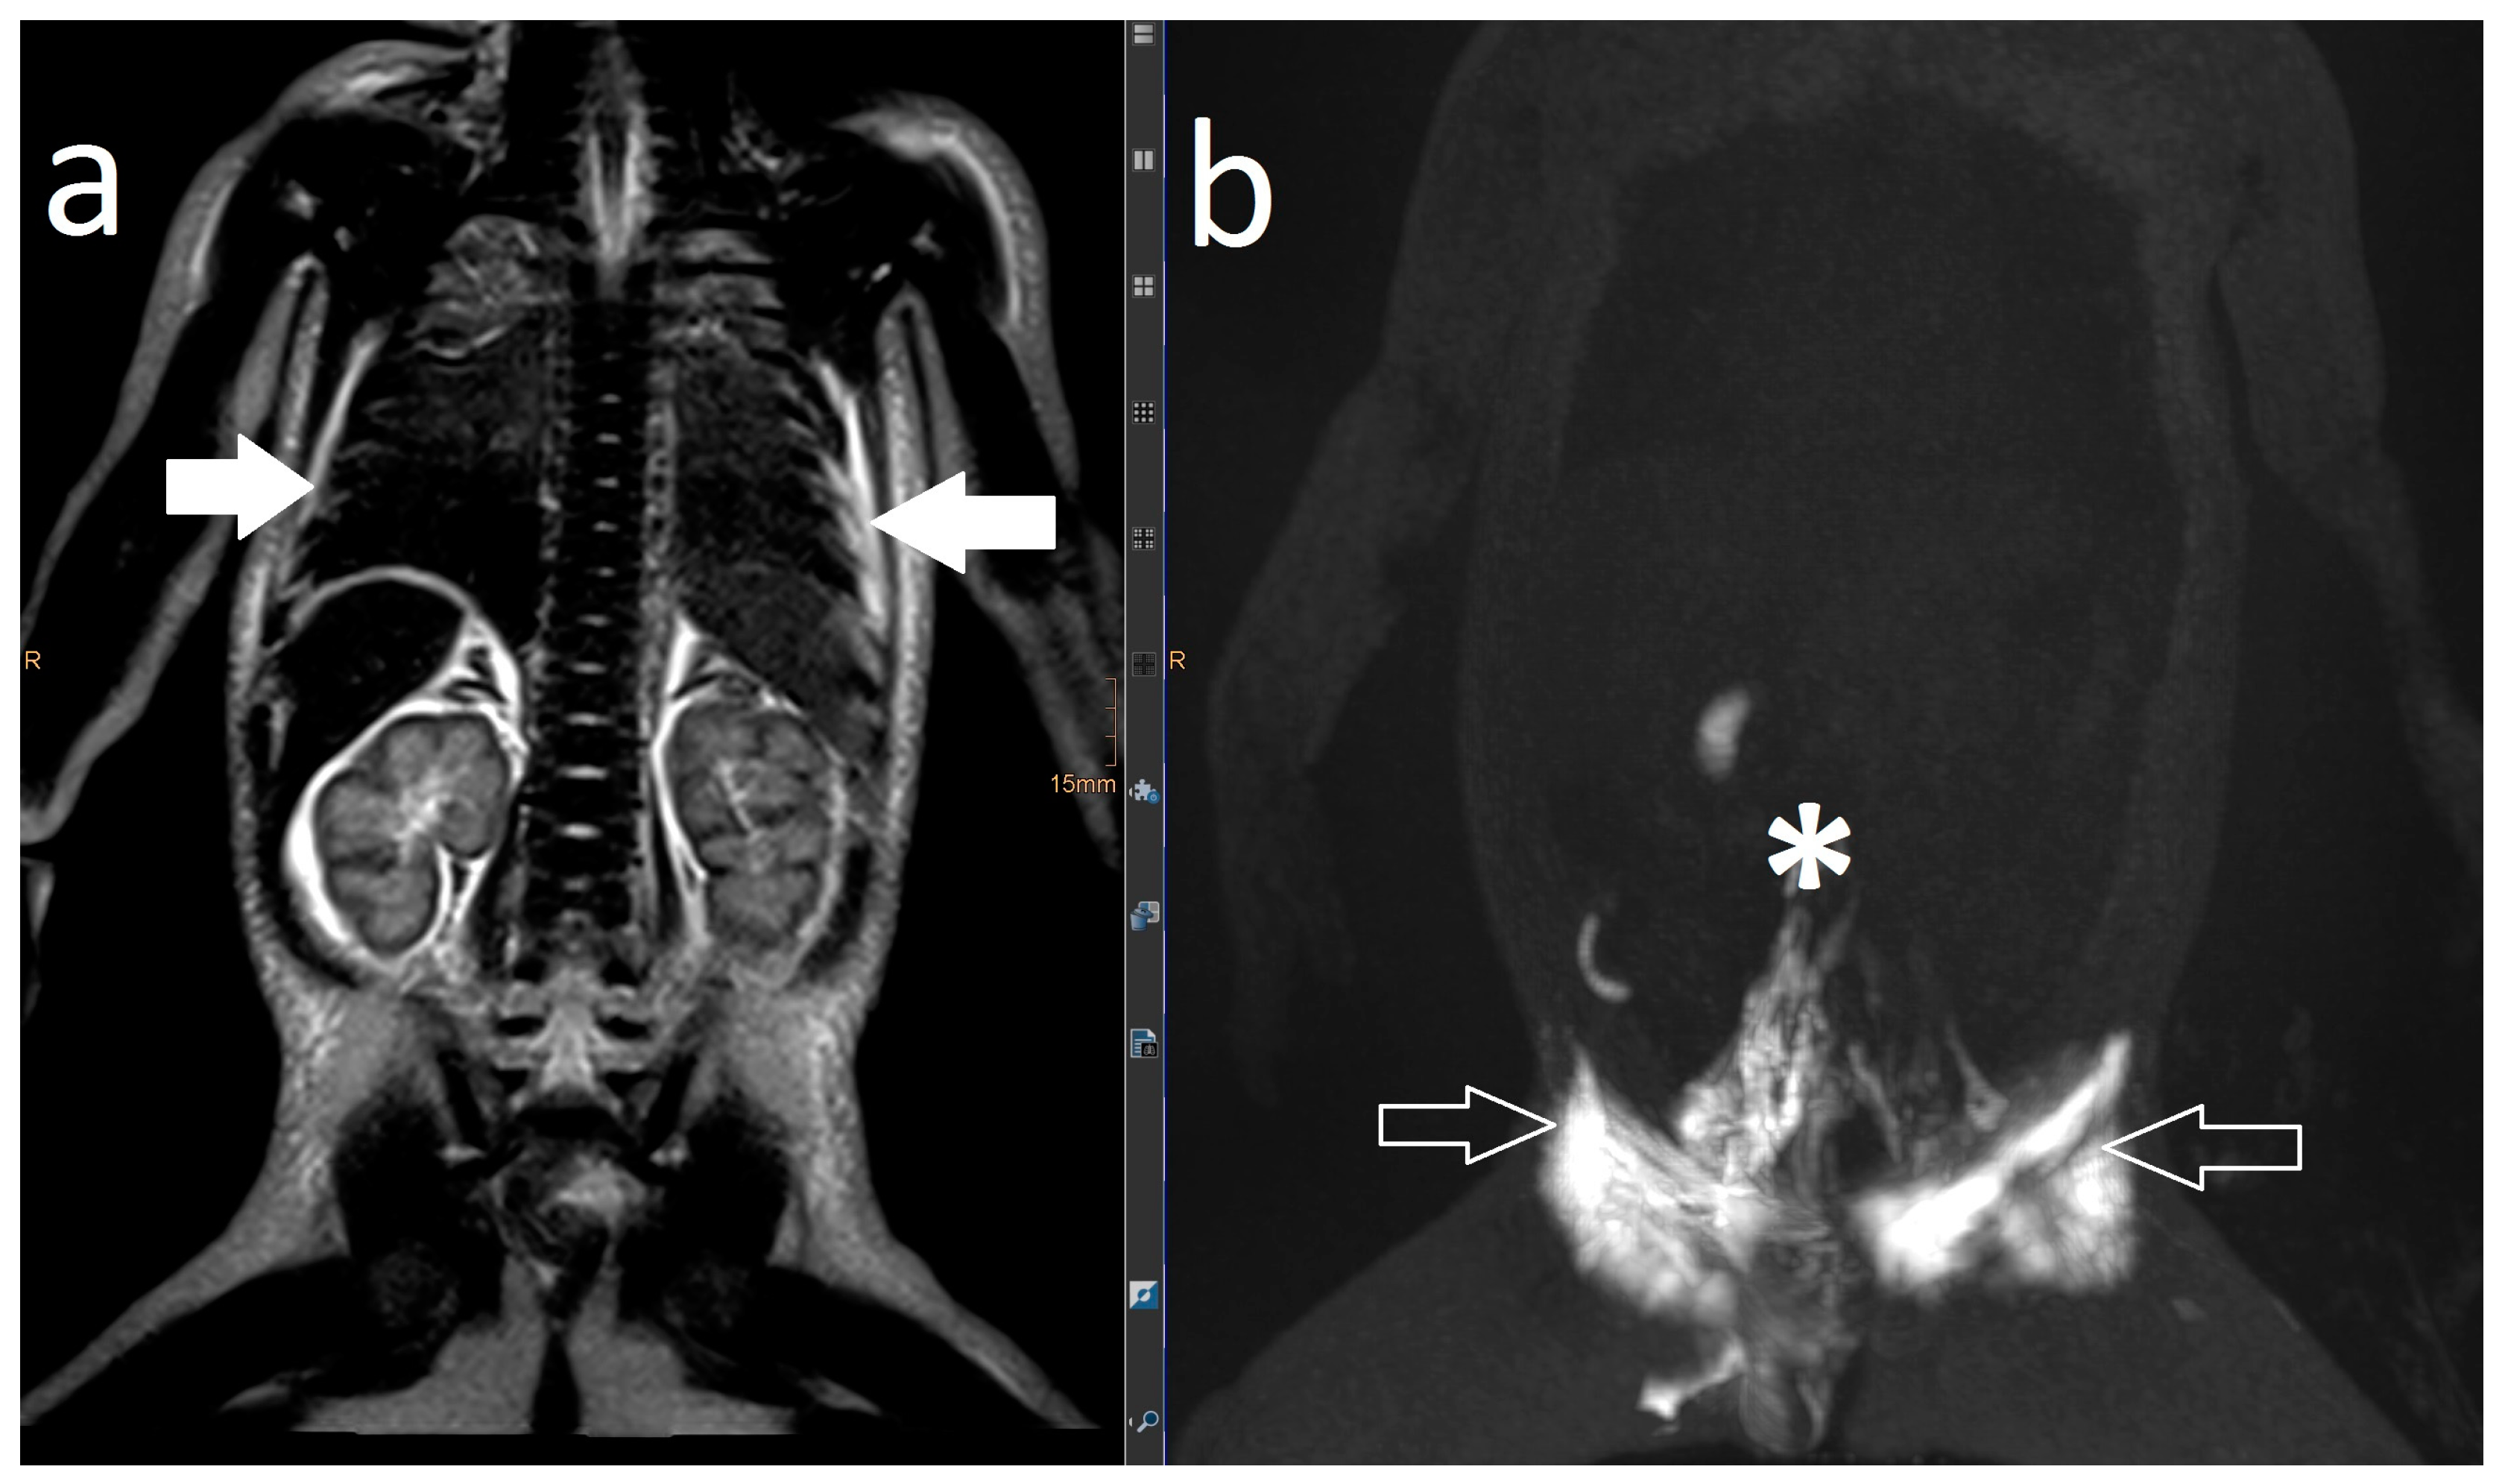

| 1 | 4 | increased signal neck, mediastinum, hilum, perihilar, interstitial lung parenchyma, pleural effusion | abnormal, perfusion to the lung, intercostal flow, dilated lymphatic networks in neck, mediastinum, hilum and perihilar | in the right apical lung | diuretics, sildenafil, non-invasive ventilatory support | lymphatic intervention | Resolution of CT (FU: 10 m, cessation of ventilatory support. |

| 3 | 4 | increased signal neck, mediastinum, hilum, interstitial lung parenchyma, body wall edema, pleural effusion, ascites | abnormal, perfusion to the lung, intercostal flow, dermal backflow, | TV 6–9 bilateral into the lung | diuretics, sildenafil, MCT diet, non-invasive ventilatory support | no | persistent chylothorax, respiratory support |

- Biko, D.M.; Reisen, B.; Otero, H.J.; Ravishankar, C.; Victoria, T.; Glatz, A.C.; Rome, J.J.; Dori, Y. Imaging of central lymphatic abnormalities in Noonan syndrome. Pediatr. Radiol. 2019, 49, 586–592. [Google Scholar] [CrossRef] [PubMed]